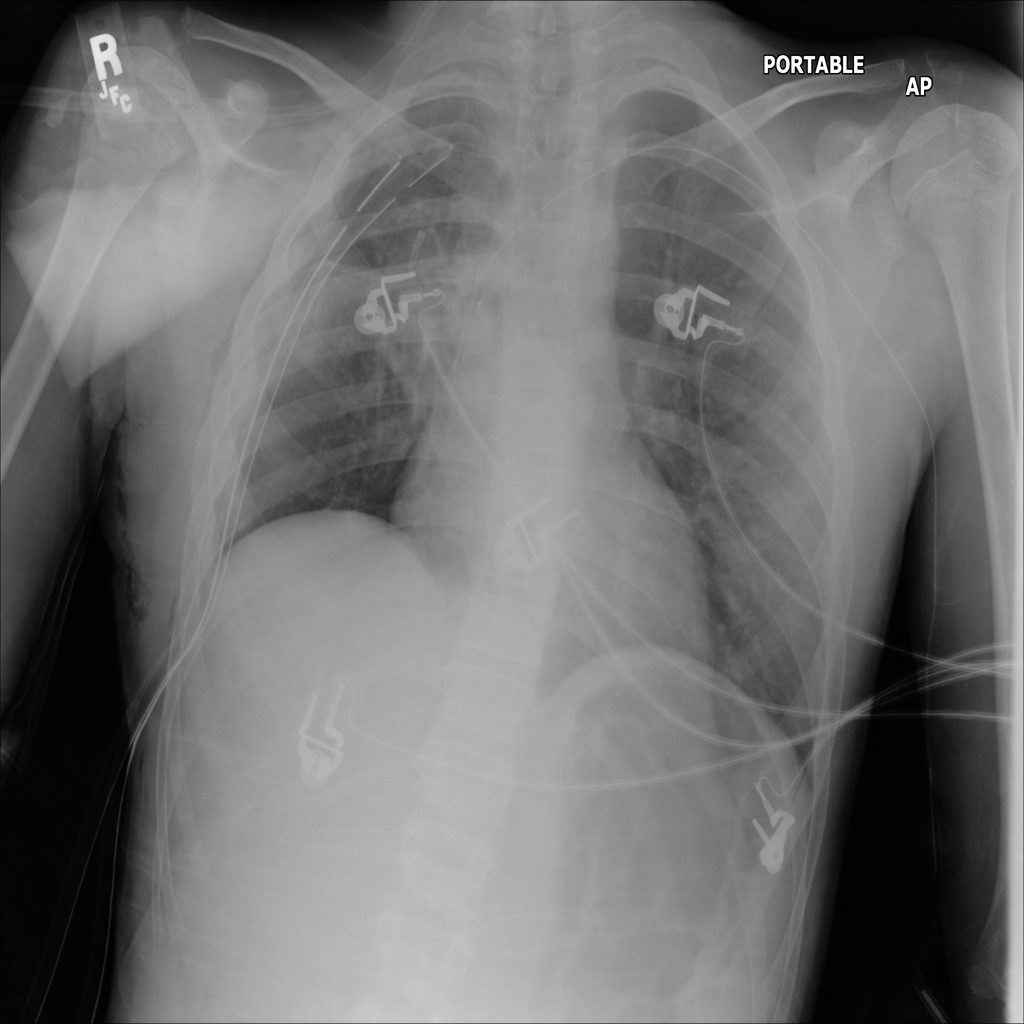

PAT-55FC · IMG-030Emphysema

PAT-55FC · IMG-030

AP